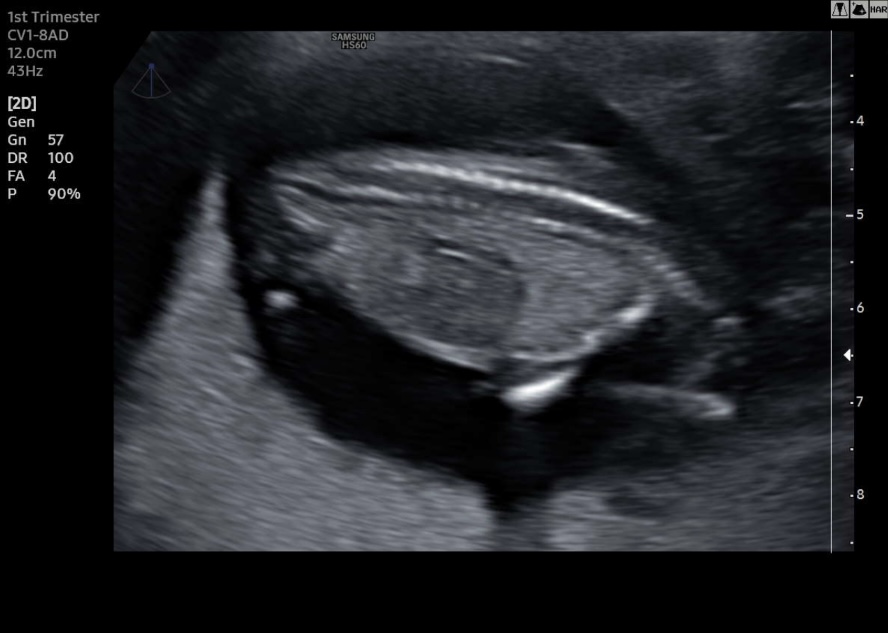

I have found more pictures that are maybe useful. Unfortunately no clear picture from the side with a nub what makes me think boy. Please help me with your guesses:-)Attachment 43795Attachment 43796Attachment 43797Attachment 43798Attachment 43799Attachment 43800Attachment 43801Attachment 43802

Also found this image of a possible potty shot. Any boy or girl parts visible over here?

There is no nub visible on any of these. I just can't guess based on any of these photos.